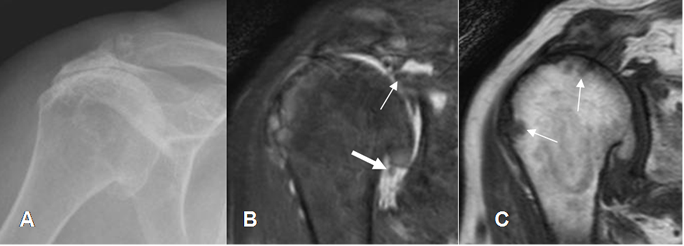

El hombro de milwakee, es una entidad que afecta mas frecuentemente a las mujeres y ocasiona artritis rápidamente progresiva. Generalmente existe un antecedente traumático. Hay ruptura completa del manguito rotador, cambios degenerativos, derrame articular, hiperplasia sinovial con cuerpos libres y destrucción del cartílago y el hueso subcondral. Estos hallazgos pueden ser identificados con Rx, Ecografía y RM. (5). (Fig 16).

Fig 16. Hombro de milwakee.

A: Rx AP de hombro. Pérdida del espacio acromiohumeral, con esclerosis asociada.

B: RM coronal STIR. Ruptura retraída del supraespinoso (Flecha delgada), con signos de sinovitis y cuerpos libre (Flecha gruesa).

C: RM coronal en T2. Erosión y lesiones osteocondrales de la cabeza humeral.